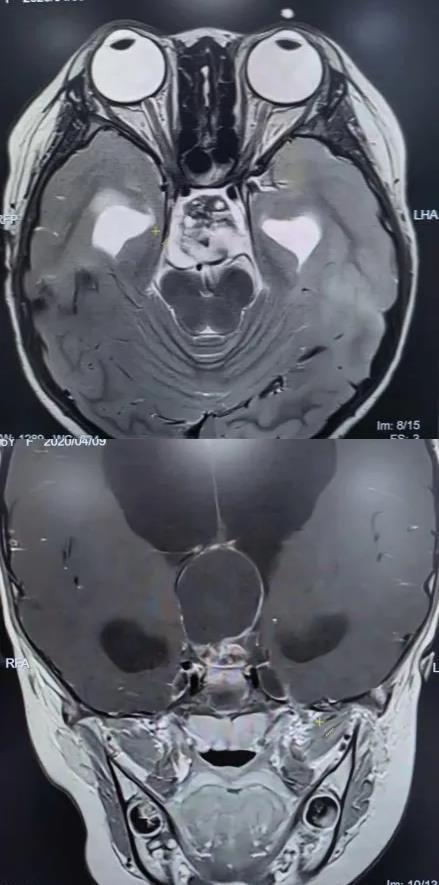

术后垂体MRI增强检查

手术中,团队借助高清4K神经内镜,凭借精湛的显微操作技术,细致分离肿瘤与周围神经、血管的粘连。历经3小时,肿瘤被完整切除,下丘脑、垂体柄、视神经等重要结构均得到完好保护。术后病理确诊为颅咽管瘤。

在医护团队的精心照护下,欢欢神经功能障碍明显改善,视力逐渐恢复,头痛症状完全消失,梗阻性脑积水得到有效缓解。之后顺利拔除脑室引流管,未出现脑脊液漏、感染等并发症,内分泌功能也通过药物获得精准调控。